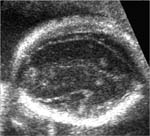

Echographiquement : - Masse hyperéchogène intra-ventriculaire aux contours irréguliers avec hydrocéphalie.

- Existence d’une artère affluente au doppler couleur.

- Localisation : * Atrium du ventricule latéral